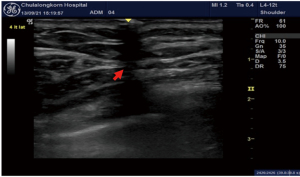

In this study, the ultrasound technique was performed as follows: a line was initially drawn connecting the nipples, extending to anterior axillary line on both sides. The linear ultrasound probe was placed along this line to identify the most distal point of lateral border of pectoralis major muscle. Once identified, the probe was adjusted so that the border aligned with the central marker (mid-probe), and this point was marked on the skin (Figure 2). This marked location corresponded to the lateral pectoral border at the nipple level, perpendicular to the chest wall (Figure 3). The distance from this point to nipple was measured using a tape measure and recorded. For the inferior border, the ultrasound probe was rotated 90 degrees and placed just below the nipple, perpendicular to the initial reference line. The same measurement protocol was followed for inferior pectoral border to nipple distance.